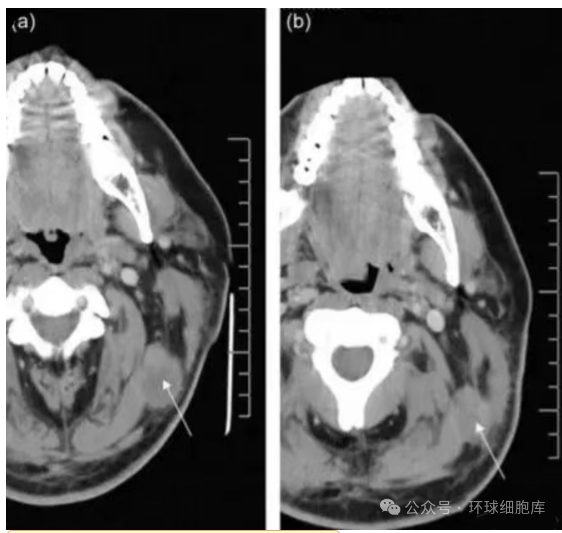

2008年,美国拉什大学医学中心的研究人员将外源扩增的NK异体细胞注入到黑色素瘤患者体内,结果发现,注入注入NK细胞后,该患者左上颈部肿瘤的体积明显降低(从3.15 cm×2.54 cm减小至2.46 cm× 1.76 cm)。同时,该研究也为外源扩增的NK异体细胞是否可以大规模应用于治疗黑色素瘤提供了一定的理论依据。

△ NK细胞治疗前后对比图